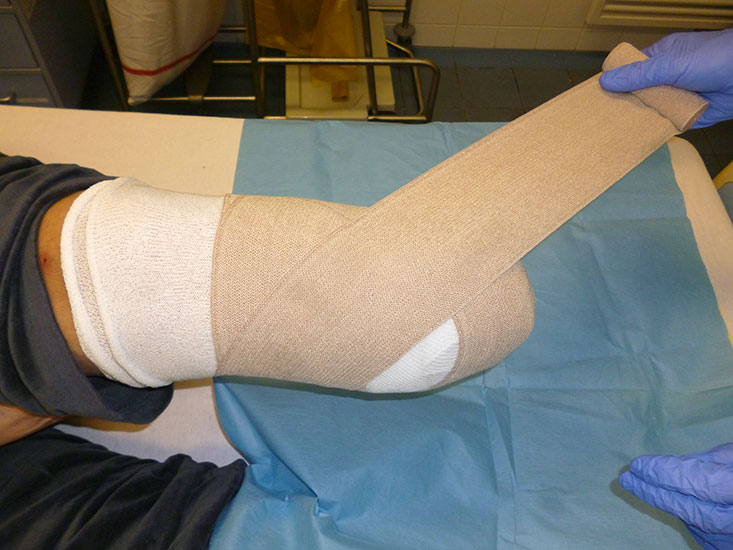

Der Amputationsstumpf wird mit einer elastischen Binde (Langzug) komprimiert. Das dient in der postoperativen Phase zur Blutstillung und im weiteren Verlauf der Stumpfkonfiguration.

Abbildung 13

Bei Amputationen im distalen bis mittleren Fuß erfolgt die Entlastung im Verbandsschuh bis zur Wundheilung. Je weiter proximal die Amputation gelegen ist, umso länger muss entlastet werden. Mit Kompressionsverbänden (Abb. 13) und ruhigstellenden Hartverbänden (Cast) kann man das Risiko einer Nachblutung verringern. Vorsicht ist bei PAVK geboten, da die Kompression Nekrosen hervorrufen kann. Drainagen werden bis zum Sistieren der Sekretion belassen.